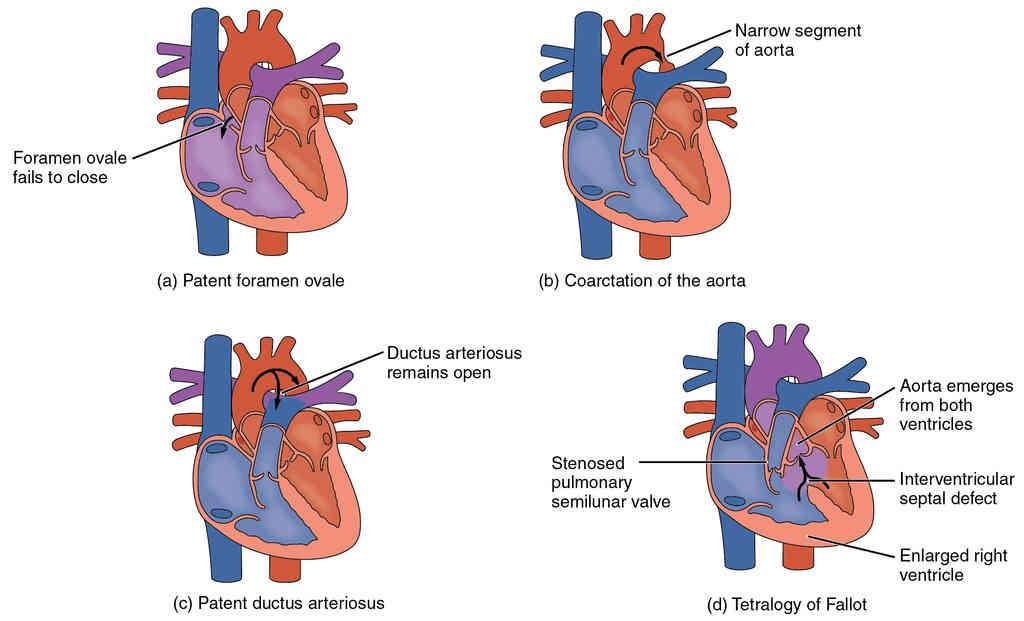

This page is under construction. For now, it is just a resource of the images found in the OpenStax Anatomy and Physiology Handbook. It wil slowly change into a revision tool. Each slide has a number. Use this to refer to the slide. When completed, it will have an unlabelled section, with labelled slides in parallel. On the unlabelled slides, write your answer and use the labelled slide to assess yourself. Keep track by also noting the number on each slide. Improvement at each attempt is important, more so than full marks on a first attempt.